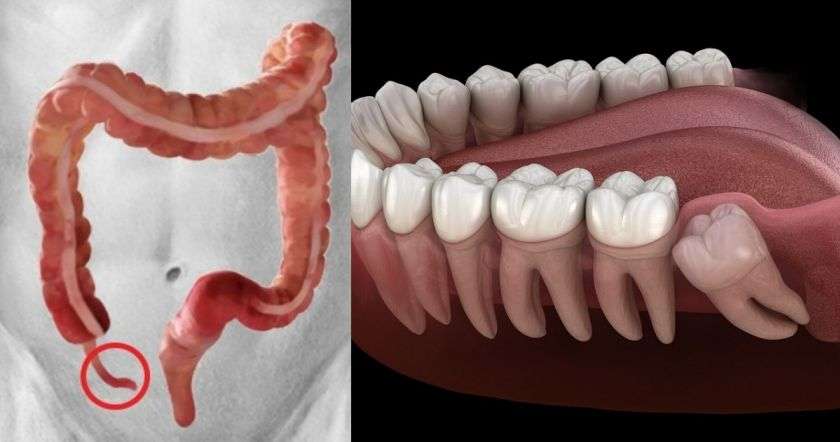

Ապենդիքս

Կույր աղիքի այս հատվածն օգնել է մեր նախնիներին մարսել կոշտ սնունդը: Սակայն այսօր մարդիկ դրա կարիքն այլևս չունեն: Հաճախ կլսեք, որ մարդիկ հեռացնում են կույր աղիքի այս ծայրային հատվածը: Նախկինում, երբ բժշկությունն այնքան էլ զարգացած չէր, ապենդիքսի պատճառով բազմաթիվ մարդիկ էին մահանում:

Իմաստության ատամ

Նախկինում իմաստության ատամները կարևոր գործառույթ էին իրականացնում. դրանք օգնում էին ավելի լավ ծամել սնունդը, և սա ևս կապված էր չափազանց չոր սնունդ ընդունելու հետ: Իսկ այսօր շատ երեխաներ անգամ ծնվում են առանց իմաստության ատամների: Առաջ մարդկանց ծնոտներն ավելի մեծ էին ու հարմարավետ՝ իմաստության ատամների տեղավորման համար: Սակայն այսօր մեր ծնոտների չափերը փոքրացել են, հետևաբար այդ ատամների համար բավարար տեղ այլևս չկա: Այսինքն՝ դրանք չեն աճում այնտեղ, որտեղ հարկավոր է: